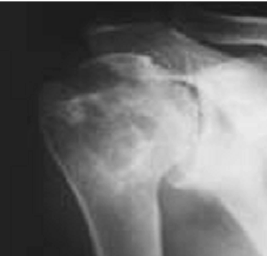

Fig 65 A. Artritis séptica residual.

Rx AP. Disminución, irregularidad y esclerosis del espacio glenohumeral, como secuelas de artritis infecciosa.